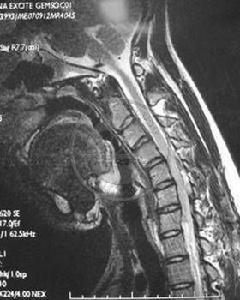

(1)動力學因素:Hiarayama等認為發病機制為反覆的屈頸動作或長期的維持屈頸姿勢導致已前置易位的硬脊膜從後方推壓頸脊髓,從而造成循環障礙,下頸髓前角運動細胞慢性缺血壞死。由此臨床試用頸圈治療本病有效,支持了一機制的可能。

(3)無彈性、限制性的硬脊膜壓迫:Konno等認為平山病是異常的硬脊膜牽拉限制作用,不僅在直立位時影響,而且在屈頸時加重脊髓的損傷。頸脊膜的松解成形手術明顯的近期和遠期效果也證實了這一觀點。

平山病的病程自限,預後是良好的。目前有以下的治療方法:(1)頸托治療:早期診斷早期帶頸托治療,能縮短病程,緩解臨床表現。建議必須儘可能長時間帶頸托治療。(2)手術治療:研究表明做硬脊膜成形術加脊髓松解術,能改善近期和遠期效果。